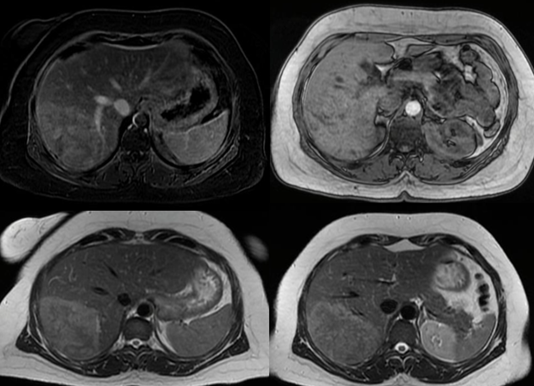

Resonancia Magnética: se destaca una imagen focal bien delimitada en el segmento 6 y 7 levemente Hiperintensa en T2, isointensa en T1, realza en fase arterial e isointensa en fase venosa y tardía salvo en sector interior hipointenso. Mide 111 x 70 x 125 mm sin dilatación de la vía biliar. Se informa como probable Adenoma esteatósico. (Figura 2).